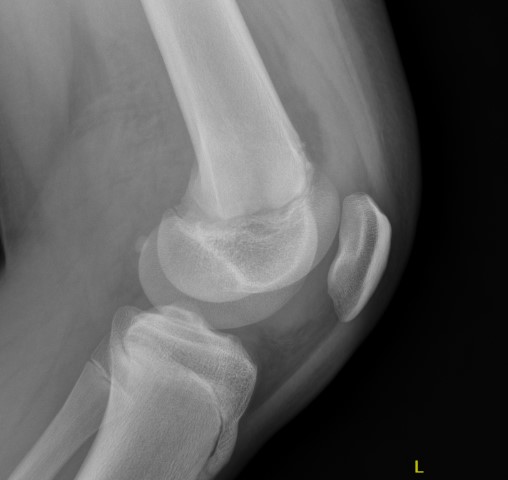

Xray

Salter Harris I

Salter Harris II